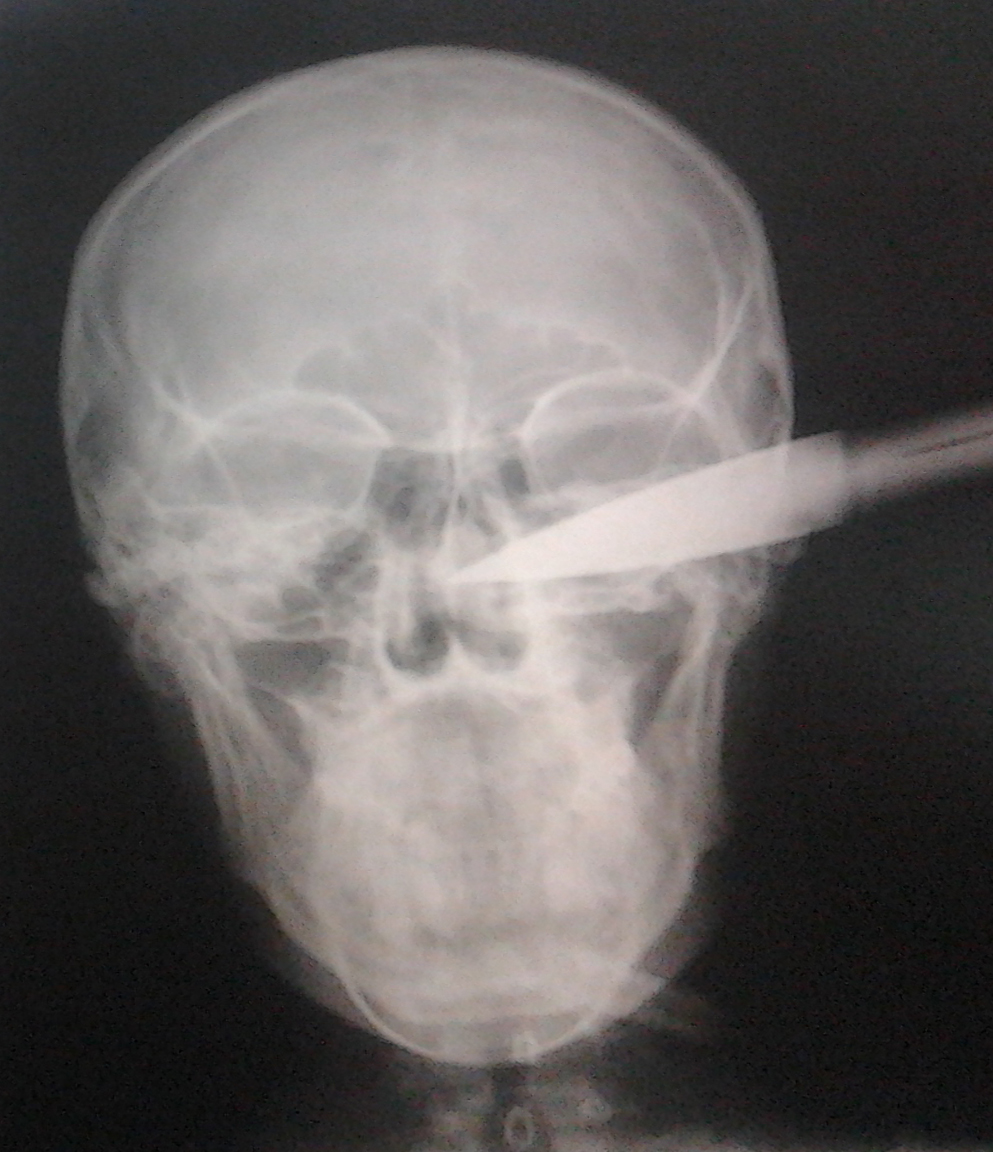

Un tanar de 20 de ani a uimit medicii! Barbatul a ajuns la spital cu o sabie efectiv infipta in cap! Dupa o operatie care a durat 45 de minute, verdictul a fost incredibil: leziunile au fost minore, iar in patru zile omul a plecat acasa!

I.A.G. (20 de ani) a fost externat din spital dupa patru zile si va ramane, cel mai probabil, in istorie drept barbatul care a trait dupa ce o sabie i-a fost infipta in cap. In ciuda faptului ca lama armei i-a patruns in craniu aproximativ sase centimetri, nici un element vascular nu a fost atins, au sustinut surse medicale.

Scandalul s-a petrecut noaptea, iar unul dintre inculpati a lovit victima cu intentia de a o omori. Cert este ca planurile le-au fost date peste cap de …destin! Barbatul care parea sa nu aiba nicio sansa de supravietuire, a scapat aproape nevatamat si dupa patru zile a fost externat. Radiografia e socanta si arata cat de aproape a fost, de fapt, tanarul de moarte si ce miracol e ca a supravietuit. (A.S.)